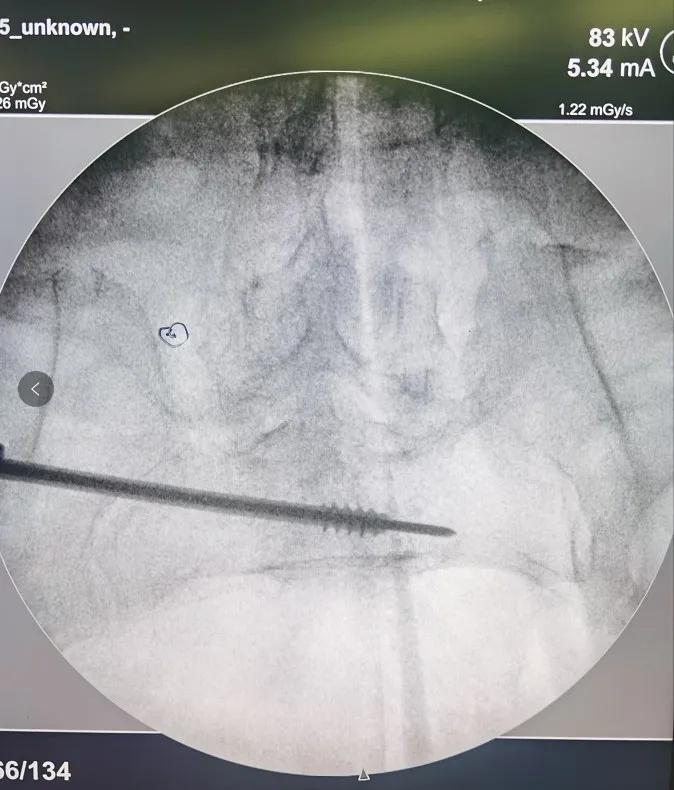

病人王**,男性,78岁,因摔伤致骨盆前后环骨折入院,患者手术意愿强烈,鉴于患者年龄较大,经科室内讨论,决定给予患者闭合复位经皮微创骶髂螺钉、耻骨支螺钉内固定术,在刘德强主任的指导下,都芳涛、方继锋、范孟坡、刘斌医师治疗团队,结合患者术前影像学资料,精确规划进钉点、进钉角度,在腰麻下进行手术治疗,术中反复进行C臂多角度透视,确定螺钉位于安全区内,顺利置入螺钉,术中出血约10毫升。目前患者在张来民护士长、路秀娥专职护师的精心护理下,恢复满意。

术中影像